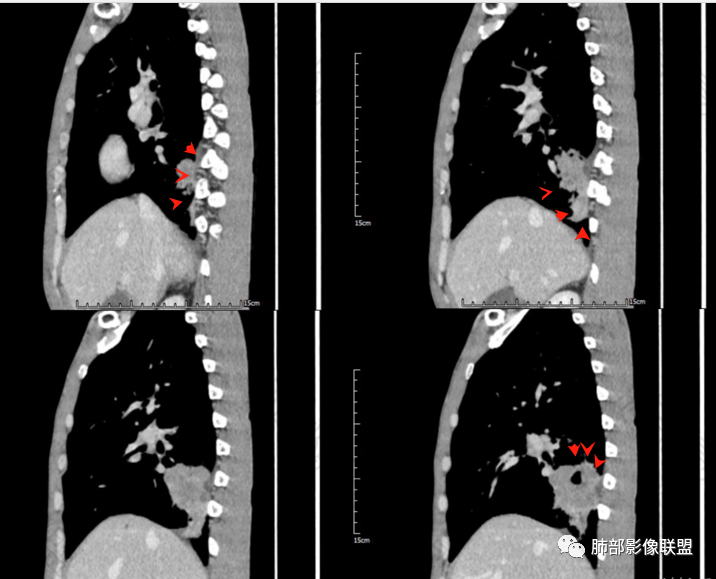

加餐病例

病检结果:鳞癌

甄德强老师分析

多发小灶性坏死。强化程度轻,几乎观察不到完整血管影。

浅分叶,边界清

近端支气管堵塞

肺气肿背景

综上考虑鳞癌,鉴别低分化腺癌

一般来讲,鳞癌收缩力弱,胸膜凹陷及牵拉少见,空洞坏死多见,而此例出现了“胸膜凹陷”,如下图:

这种特点在鳞癌比较多见  周围型鳞癌经常这个形态,外周有类似喇叭样收缩形态,考虑周围型鳞癌引起局部肺不张,所以有远侧内收而缺乏侧面收缩力。

回头看发现肿块近肺门侧边缘清楚,而远肺门侧边缘模糊,多考虑肿块阻塞支气管引起的阻塞性炎症,支持周围性鳞癌引起局部肺不张观点,两者形态相似,易与胸膜凹陷征混淆,小编认为,因肺不张为实变的肺组织,而胸膜凹陷为脏层胸膜受肿块牵拉凹陷形成的含液腔隙,故鳞癌形成的“胸膜凹陷”其密度较高,多为实性密度,而真正的胸膜凹陷征其内部密度较低,多为液体密度。